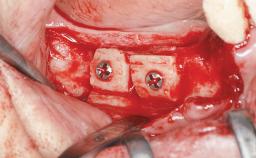

Staged bone augmentation of the alveolar ridge is indicated whenever a proposed implant site is deficient and will not support implant placement with simultaneous grafting. This is particularly true of healed sites presenting with facial flattening of the ridge. Since primary stability cannot possibly be achieved in this situation, it is recommended to use a staged approach with guided bone regeneration (GBR) for correct three-dimensional placement of the implant. In the anterior maxilla, staged GBR procedures are conducted not only to provide adequate bone volume for implant placement but also to restore a proper and stable contour of the orofacial ridge for improved long-term esthetics. A case is presented that demonstrates the technique for single-tooth replacement utilizing a staged approach with a particulate grafting material. A 50-year-old man whose tooth 11 was missing presented for consultation to the Center for Implant Dentistry in January 2010.